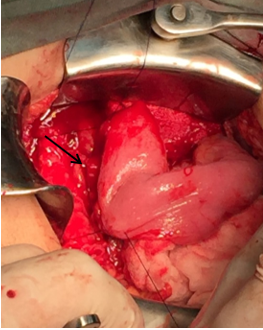

Fig. 2: Anastomosis Wirsung-yeyunal. (* Asa Yeyunal, flecha: anastomosis Wirsung-Yeyunal)

Sección del intestino delgado a nivel de la segunda asa yeyunal, con cierre del extremo distal de la misma y ascenso del asa por vía transmesocólica. Apertura del asa por su borde antimesentérico y confección de la anastomosis yeyuno-pancreática (Wirsung) latero-lateral con puntos separados con poliglactina en 2 planos (Figura 3).